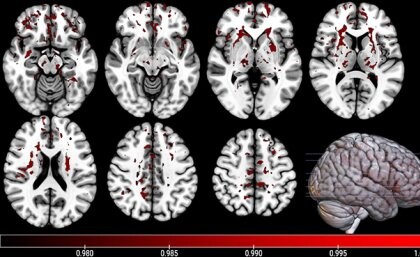

Separately to this, researchers at The University of Queensland (UQ) have used an advanced imaging technique, known as neurite orientation dispersion and density imaging (NODDI), to predict the recovery of children from mild TBI. Mild TBI includes concussion and can result in headaches, difficulty sleeping and/or problems with attention and memory for several months — problems which are caused by disruption to communication between different areas and networks in the brain.

“Our study was the first to use … NODDI to investigate the changes in those networks over time in children with mild traumatic brain injury,” said PhD candidate Athena Stein, who noted that the technology provides more detailed information on structural damage in the brain than traditional magnetic resonance imaging (MRI).

The researchers ultimately investigated changes in the brain over the three months following injury in 80 children who had ongoing injury-related symptoms, and also tested 32 children who had already recovered from injury and compared the results to 21 healthy control children. According to their results, published in the Journal of Neurotrauma, “The children with ongoing symptoms following mild TBI had significantly lower structural integrity and more microstructural damage in their brain networks compared to the healthy controls,” Stein said.